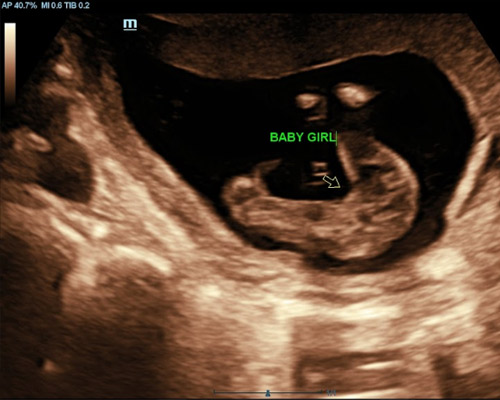

A gender scan near Wakefield is a specialised ultrasound used to determine whether you are expecting a boy or a girl. Many parents choose this scan to find out earlier rather than waiting for their routine hospital appointment.

During the scan, the sonographer carefully checks your baby’s position and uses ultrasound imaging to identify the gender as clearly as possible. Alongside this, you will also have the chance to see your baby moving, which adds to the experience.

- 2D ultrasound to determine your baby’s gender

From around 15 weeks, gender can usually be identified with a high level of accuracy, depending on your baby’s position during the scan.

The sonographer uses ultrasound imaging to examine the relevant area and determine whether you are expecting a boy or a girl.